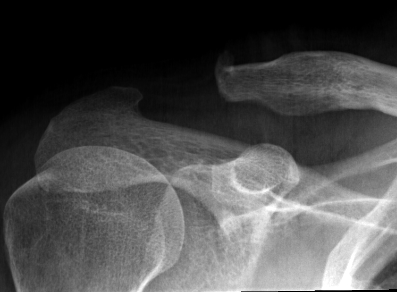

Neer Classification

Fracture lateral to the CC ligaments Non displaced

Fracture medial to the CC ligaments CCL ligaments attached to lateral fragment Medial fragment displaced superiorly |

Between conoid and trapezoid Conoid disrupted Trapezoid remains attached to the lateral fragment |

Lateral to CC ligaments Intra-articular extension Stable |

Periosteal sleeve disruption Pediatric Medial fragment displaced |

Comminuted Type II Medial fragment displaced |

Type I

Type II

Type V